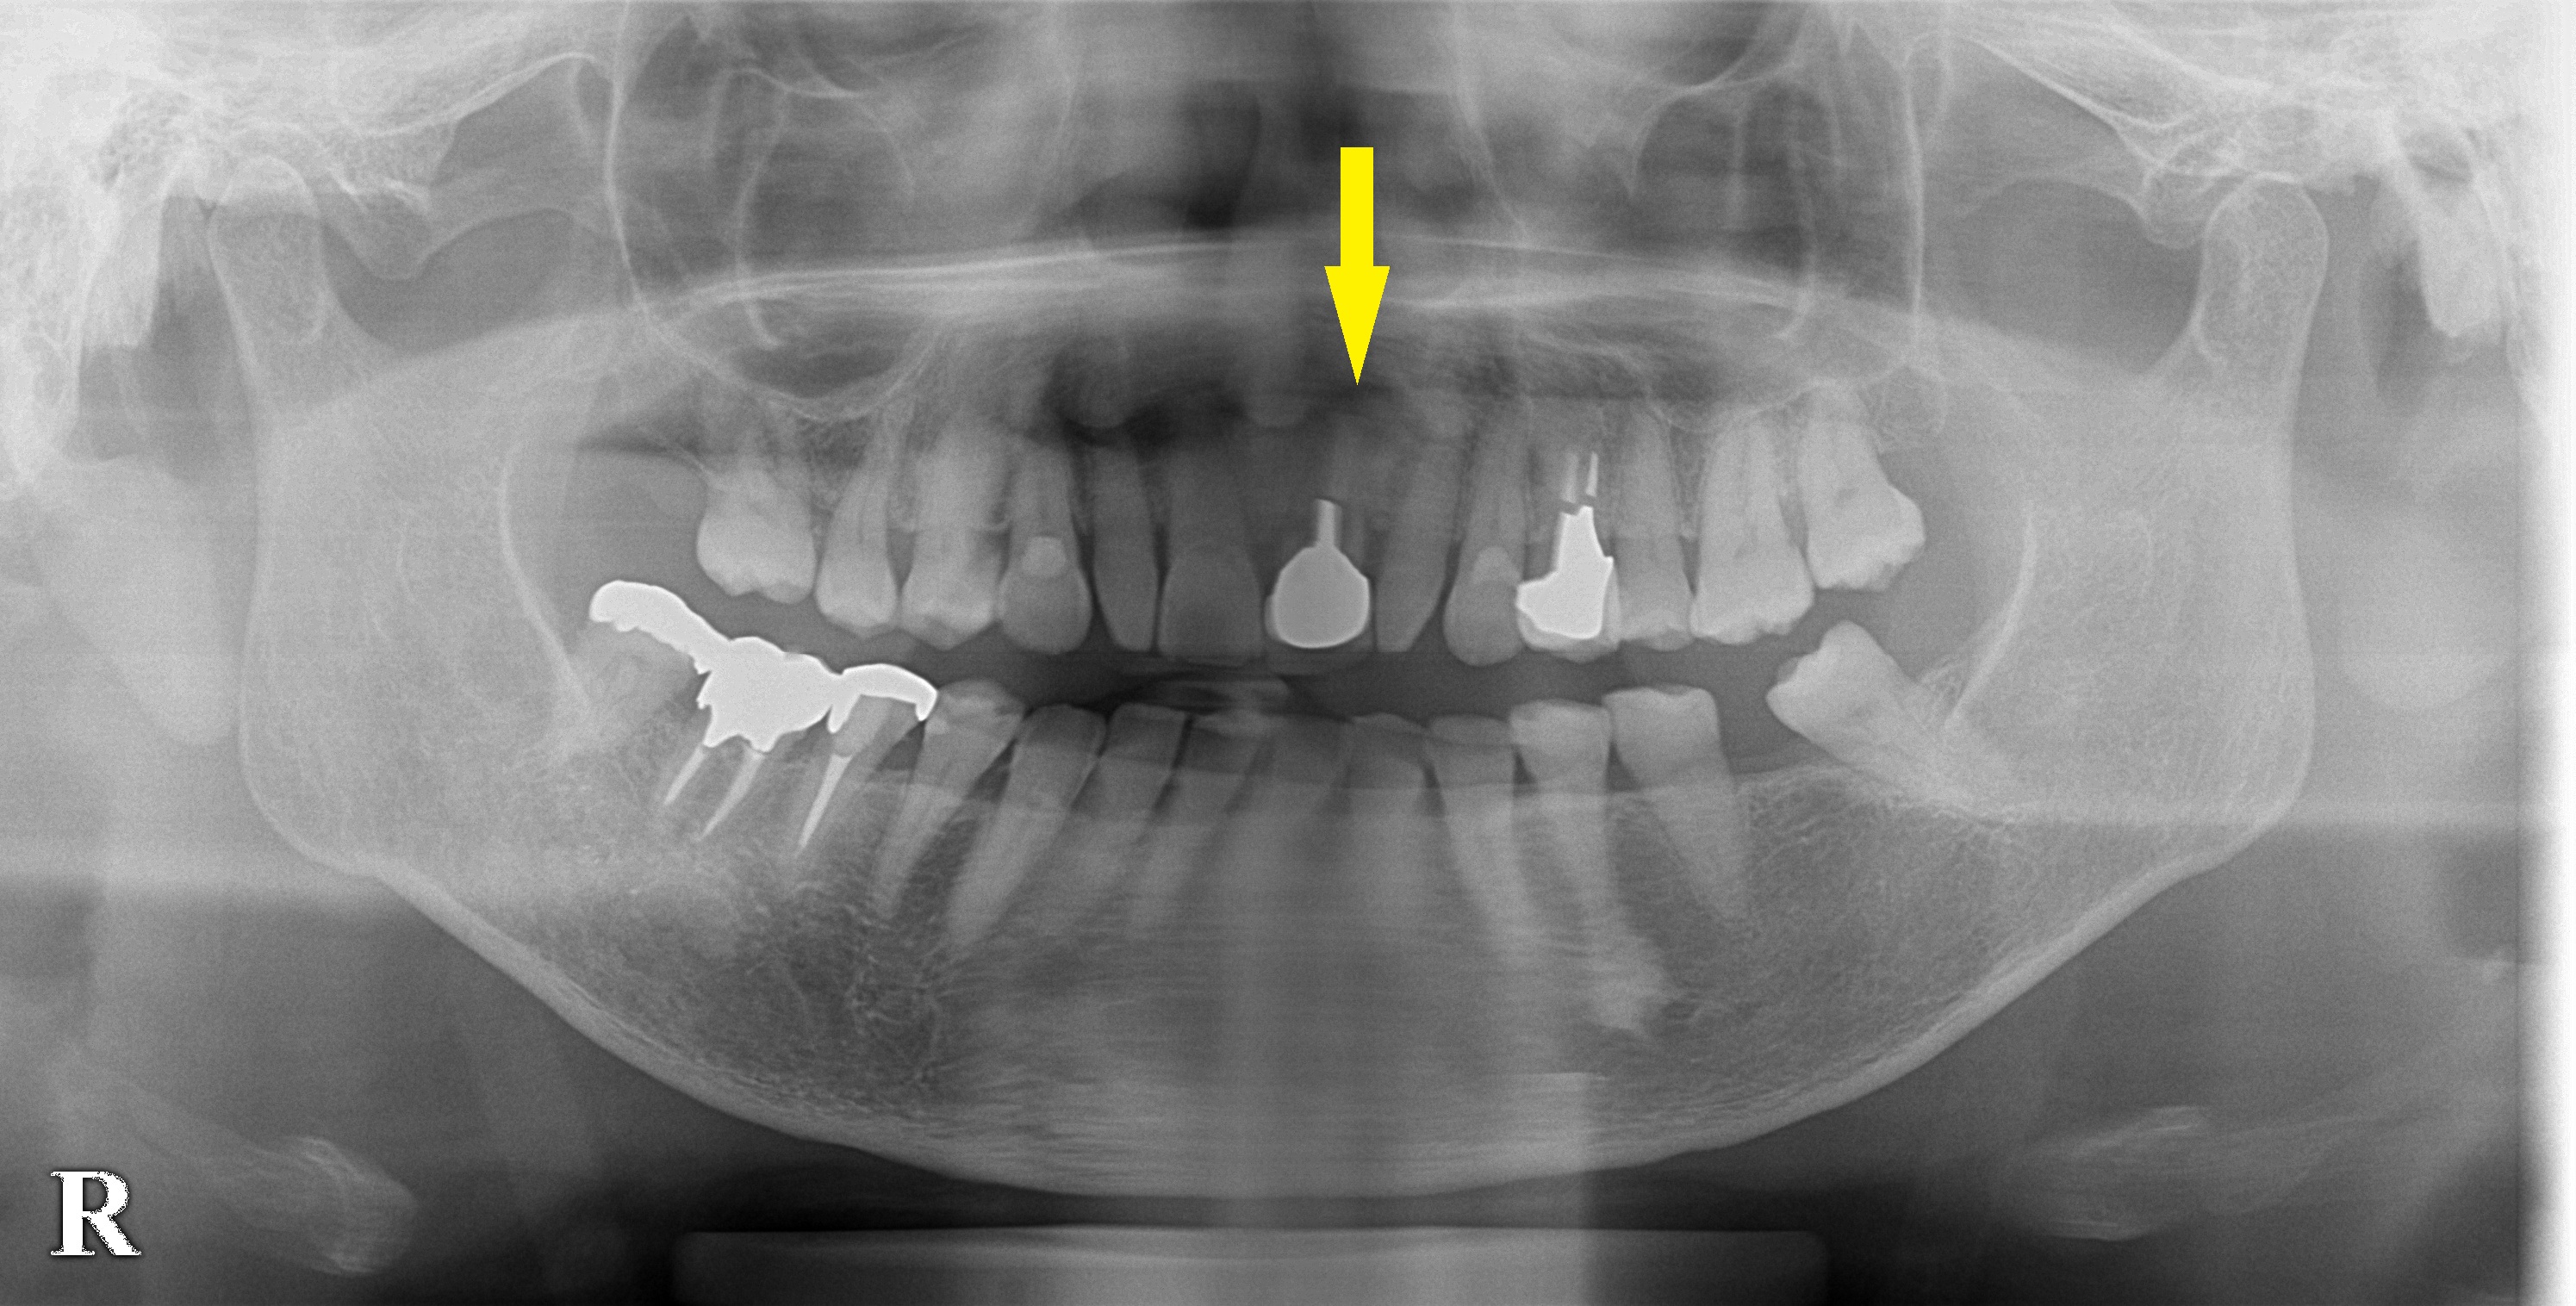

レントゲン写真、CTを撮影してみると、根管治療された歯の歯根周囲の骨が、大きく吸収されてしまっていました(下段左の写真)。

下段右が術後のレントゲン写真で、

インプラントが抜歯した部位に埋入されインプラントの外側には填入した人工骨が認められます。